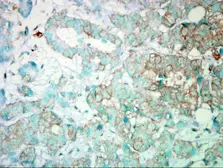

Images